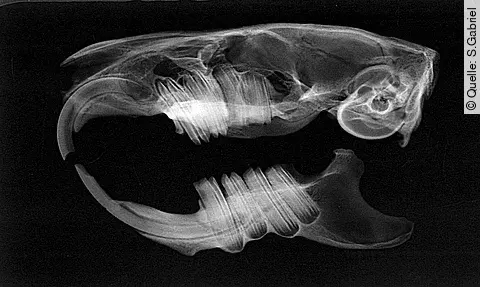

Fehlstellungen, lockere Zähne oder Kanten und Spitzen, die die Schleimhäute verletzen: Zahnprobleme gelten bei Kaninchen als häufigster Grund, zum*zur Tierärzt*in zu gehen. Ähnlich wie bei Meerschweinchen, Chinchillas und Degus wachsen bei den Tieren sowohl die Schneide- als auch die Backenzähne dauerhaft nach und werden über das Kauen von rohfaserigem Futter abgerieben. Ob Zahnprobleme vorliegen, können Halter*innen an einigen Symptomen erkennen.

Wenn Halter*innen mögliche Zahnprobleme feststellen, ist die gewohnte Tierarztpraxis die erste Anlaufstelle. Dort kann das betroffene Tier schnell untersucht werden und bei Bedarf an einen Spezialisten weitergeleitet. Für die detaillierte Untersuchung und Behandlung werden Kaninchen, Degu und Co. narkotisiert. Das vermeidet unnötigen Stress beim Tier und senkt das Risiko für Verletzungen.